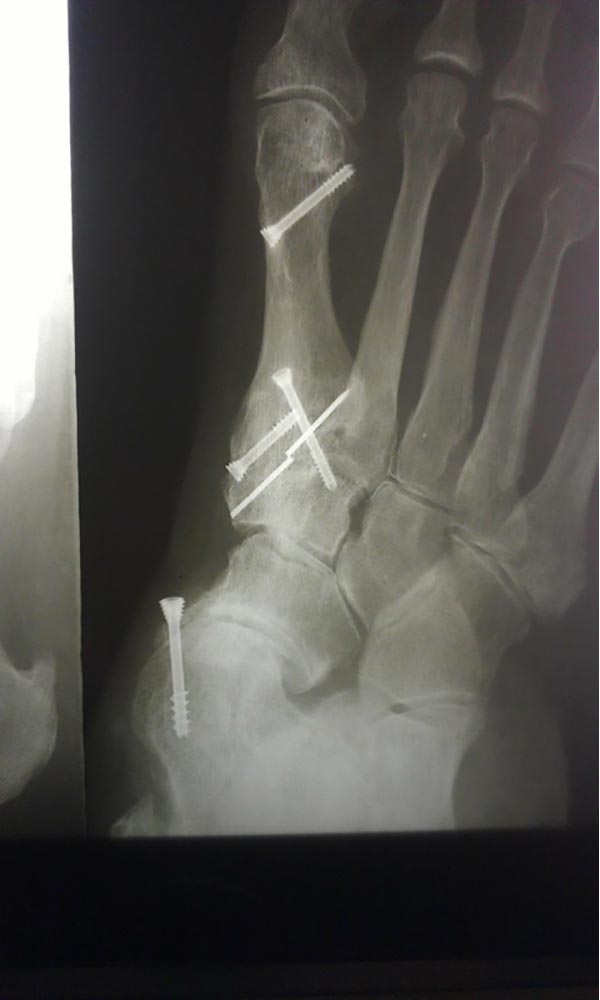

"Surgical misadventure" by another surgeon about 8 years ago. The wrong fixation was used for a flatfoot repair, & the deformity was not corrected. Patient came in with severe foot & ankle pain, with no arch at all. She was unable to play with her grandchild because the pain was so bad, & because she felt unsteady. The old hardware was removed, a lateral calcaneal lengthening osteotomy was performed along with a medial column/1st ray realignment. The ankle was painfully arthritic, & patient elected a total ankle replacement vs. an ankle fusion. She is now able to walk pain free & play with her grandchildren!